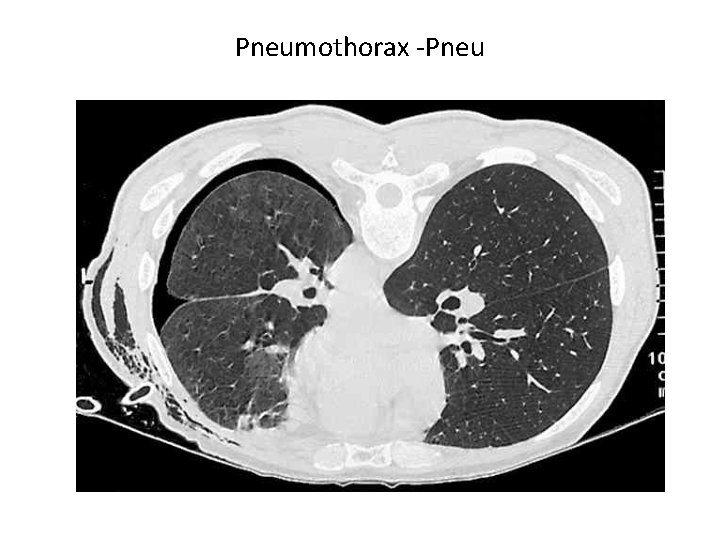

Pathologie der Pleurahöhle • Ein Pleuraerguss ist eine Flüssigkeitsansammlung im pleuralen Spaltraum • Ein Empyem ist eine Eiteransammlung im Pleuraspalt (wenn z. B. ein Lungenabszeß in den Pleuraspalt einbricht). • Pneumothorax: Wenn in den Pleuraspalt Luft tritt, hebt sich die Lunge von der Thoraxwand ab: es bildet sich der Pneuspalt eines Pneumothorax ("Pneu") aus. • Ein Hämatothorax ist eine Einblutung in den Pleuraspalt (z. B. bei Rippenfraktur). • Ein Chylothorax besteht bei Lymphe im Pleuraspalt. Die Lymphdrainage erfolgt über die viszerale Pleura. • pleuralen Tumoren • Pleuraplaques und –Verkalkungen, Pleuraasbestose

Pneumothorax -Pneu